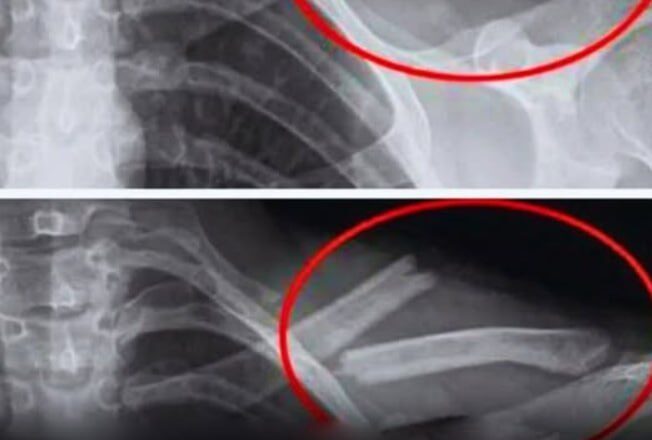

Дослідження показують, що надмірне вживання соди призводить до зниження щільності кісток, особливо у жінок. Іншими словами, ваші кістки слабшають… іноді без будь-яких симптомів, доки не станеться перелом.

Дослідження, проведене в США за участю 2500 жінок, показало, що ті, хто регулярно вживає колу, мають меншу щільність кісткової тканини стегон. І робили це несвідомо.

Дослідження, проведене серед дівчат-підлітків, також виявило зв’язок між споживанням газованої води та підвищеним ризиком переломів.